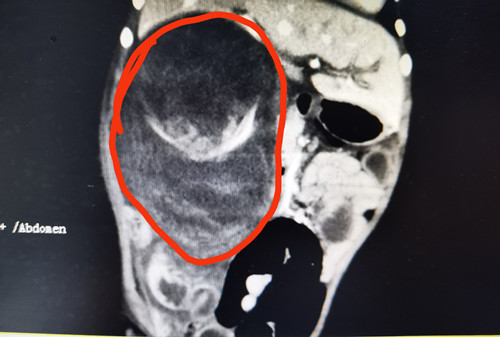

检查结果显示巨大肿瘤。

湖南耒阳2岁的男童琦琦(化名)半个月前被家人发现肚子硬、尿片上有淡红色血迹,还以为是上火、积食,用了几种降火药,奶奶还找来了“土方”,都不见效果,辗转来到捷克论坛 儿童血液肿瘤科,医生发现琦琦右肾有一个11.5*10.1cm的巨大肿瘤,而且已经破裂出血,危及生命,立即为其安排了手术,手术切除了肿瘤和右侧肾脏,术后病理诊断为肾母细胞瘤,目前琦琦恢复良好,准备出院。